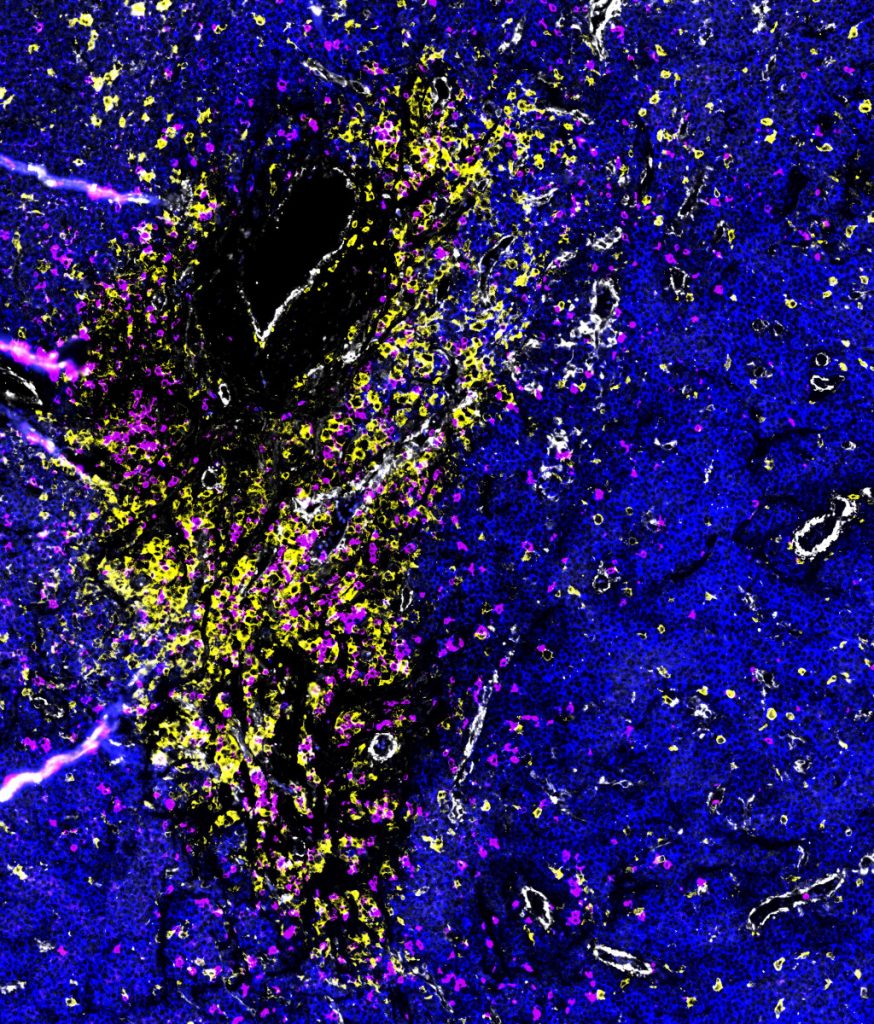

Ansammlung verschiedener Arten von Immunzellen in einem aus dem Knochen herausgebrochenen Myelomherd: T-Zellen und Natürliche Killerzellen sind pink, Makrophagen gelb dargestellt. Die umgebenden Myelomzellen erscheinen blau. Die weißen Strukturen sind Blutgefäße. Bild: Dr. Johanna Wagner, DKFZ und NCT Heidelberg, mit Hilfe räumlicher Multi-Omics Methoden aufgenommen.